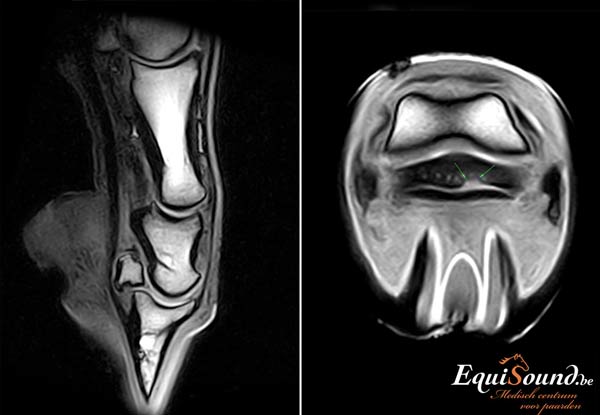

Een MRI-scanner is een geavanceerd toestel dat ons in staat stelt zowel de weke delen (ligamenten, pezen en kraakbeen) als het beenderstel van een paard in 3 dimensies te evalueren (3D). Dit is niet mogelijk met radiografie en echografie. Bovendien levert de technologie veel gedetailleerdere beelden af dan radiologie, echografie of CT. De interpretatie van de MRI-beelden wordt bij EquiSound ondersteund door ervaren MRI-specialisten Myra Barrett en Kurt Selberg vanuit de USA . Op die manier verzekert EquiSound topdiagnostiek bij uw paard vanaf het eerste uur.

Op basis van de interactie van de waterstofatomen en het magnetisch veld kunnen verschillende soorten beelden worden gemaakt (= verschillende sequenties). De sequenties kunnen in drie verschillende richtingen uitgevoerd worden. Al deze beelden samen, geven enorm veel informatie over de oorsprong en aard van de weefsels en afwijkingen.